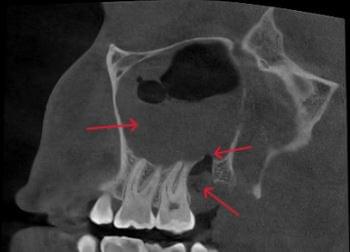

Важливо: Якщо нежить триває понад 2 тижні, з’явилася температура, набряк обличчя чи біль в очах — не відкладайте візит до ЛОРа. Раннє КТ пазух носа дозволяє виявити приховані кісти, поліпи, сторонні тіла або одонтогенний гайморит ще до ускладнень.

КПКТ (конусно-променева комп’ютерна томографія) — це 3D-знімок високої роздільної здатності. На відміну від звичайного рентгену, КТ показує:

ЛОР призначає обстеження у таких випадках:

КТ дозволяє провести віртуальну операцію: встановити імплант у програмі, виключивши будь-які ризики травмування пацієнта.